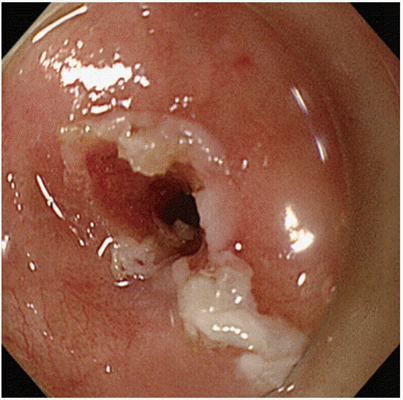

淋病圖片

淋病的症狀 (7)

淋病的症狀 (8)

淋病的症狀 (9)

淋病的症狀 (47)

淋病的症狀 (48)

淋病的症狀 (49)

淋病的症狀 (5)

淋病的症狀 (50)

淋病的症狀 (51)

淋病的症狀 (52)

淋病的症狀 (53)

淋病的症狀 (54)

淋病的症狀 (55)

淋病的症狀 (56)

淋病的症狀 (6)

淋病的症狀 (40)

淋病的症狀 (41)

淋病的症狀 (42)

淋病的症狀 (43)

淋病的症狀 (44)